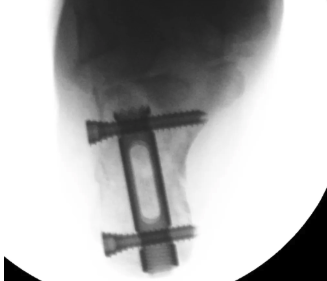

Intramedullary nail

C-Nail

Reduction

- tuberosity Schantz pin

- percutaneous reduction / K wire fixation or

- sinus tarsi approach to reduce and screw fixate posterior facet

Insertion

- below achilles tendon

- aim towards ST joint